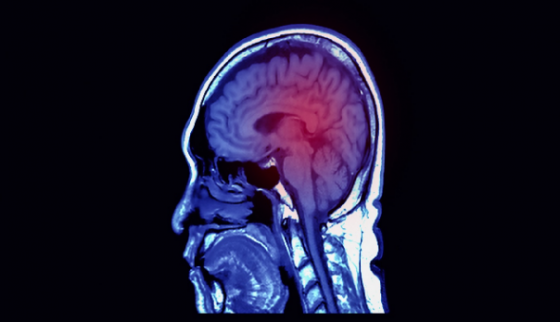

뇌경색은 뇌의 특정 부위로 가는 혈류가 차단되어 뇌세포가 손상되는 질환입니다. 이는 심각한 후유증을 유발할 수 있으며, 때로는 생명을 위협할 수도 있습니다. 이러한 뇌경색의 위험을 줄이기 위해서는 건강한 식습관이 매우 중요합니다.